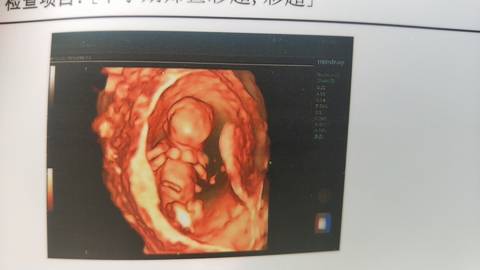

帮我看看我的NT单能不能看出男孩女孩

你好根据B超单子是看不出男女的只要宝宝健康才是我们最大的心愿不是吗?最后祝宝妈心想事成哦。

你好。我们是判断不了男宝宝跟女宝宝的,孕期定期检查,我觉得宝宝健康就好的。祝心想事成 。

#妈妈问答大赛#没有办法看出来的,而且宝宝还太小,宝宝发育健康才是最关键的,你说对吧?